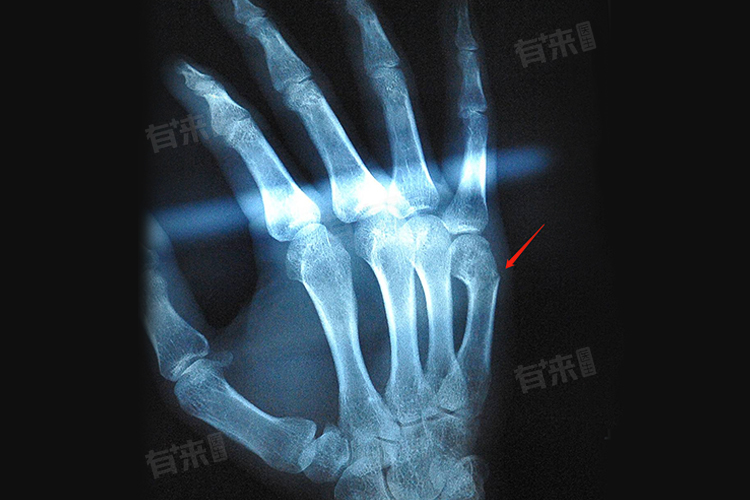

- 掌骨骨裂:掌骨在手部起到支撑和发力的作用,单一掌骨的轻微骨裂,相对不严重,对手部的整体功能影响较小,如果多根掌骨骨裂或者掌骨关键部位,如掌骨头部、基底部骨裂,可能会影响手部的握拳、抓握等功能,严重程度会增加。

- 裂缝较小:骨裂只是骨头表面出现一条很细的裂缝,没有明显的移位,这种情况相对较轻,骨骼的连续性基本保持,周围的软组织损伤也相对较小。

- 裂缝较大或伴有移位:当骨裂的裂缝较宽,或者骨裂部位出现了明显的移位,情况就比较严重,不仅会延长恢复时间,还可能导致骨折愈合不良、畸形愈合等问题,影响手部的外观和功能。